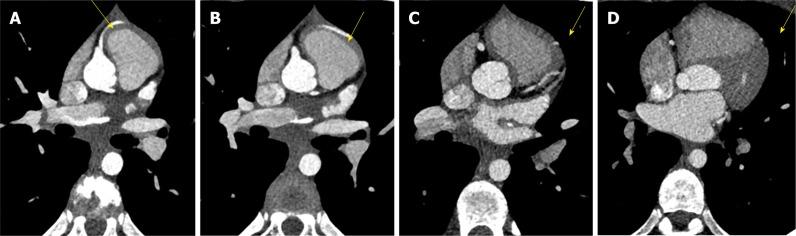

A healthy 10-year-old male patient was referred to the Radiological Department of our Institution due to no evidence of left coronary artery in echocardiographic examination. With C-MRI was detected marked myocardial trabeculation and was suspected anomalous origin and course of left circumflex (LCx) artery and of left anterior descending (LAD) artery. With third generation Dual Source C-CT 192x2-sections (SOMATOM Force, Siemens, Germany) was confirmed anomalous origin of LCx artery from right pulmonary artery associated with anomalous origin of LAD artery from right coronary artery with course in front of right ventricular outflow tract. The patient underwent surgical treatment with reimplantation of the anomalous LCX and LAD arteries into the wall of ascending aorta, with no postoperative complications. The patient remained asymptomatic and follow-up C-MRI scan four months after operation showed complete success of surgery treatment.

一名10岁健康男性患者因超声心动图检查未发现左冠状动脉而被转诊至我院放射科。通过C - MRI检测到明显的心肌小梁,并怀疑左旋支(LCx)动脉和左前降支(LAD)动脉起源及走行异常。使用第三代双源C - CT 192x2层扫描(德国西门子SOMATOM Force)证实LCx动脉起源于右肺动脉,同时LAD动脉起源于右冠状动脉且走行于右心室流出道前方。该患者接受了手术治疗,将异常的LCX和LAD动脉重新植入升主动脉壁,术后无并发症。患者仍无症状,术后四个月的随访C - MRI扫描显示手术治疗完全成功。